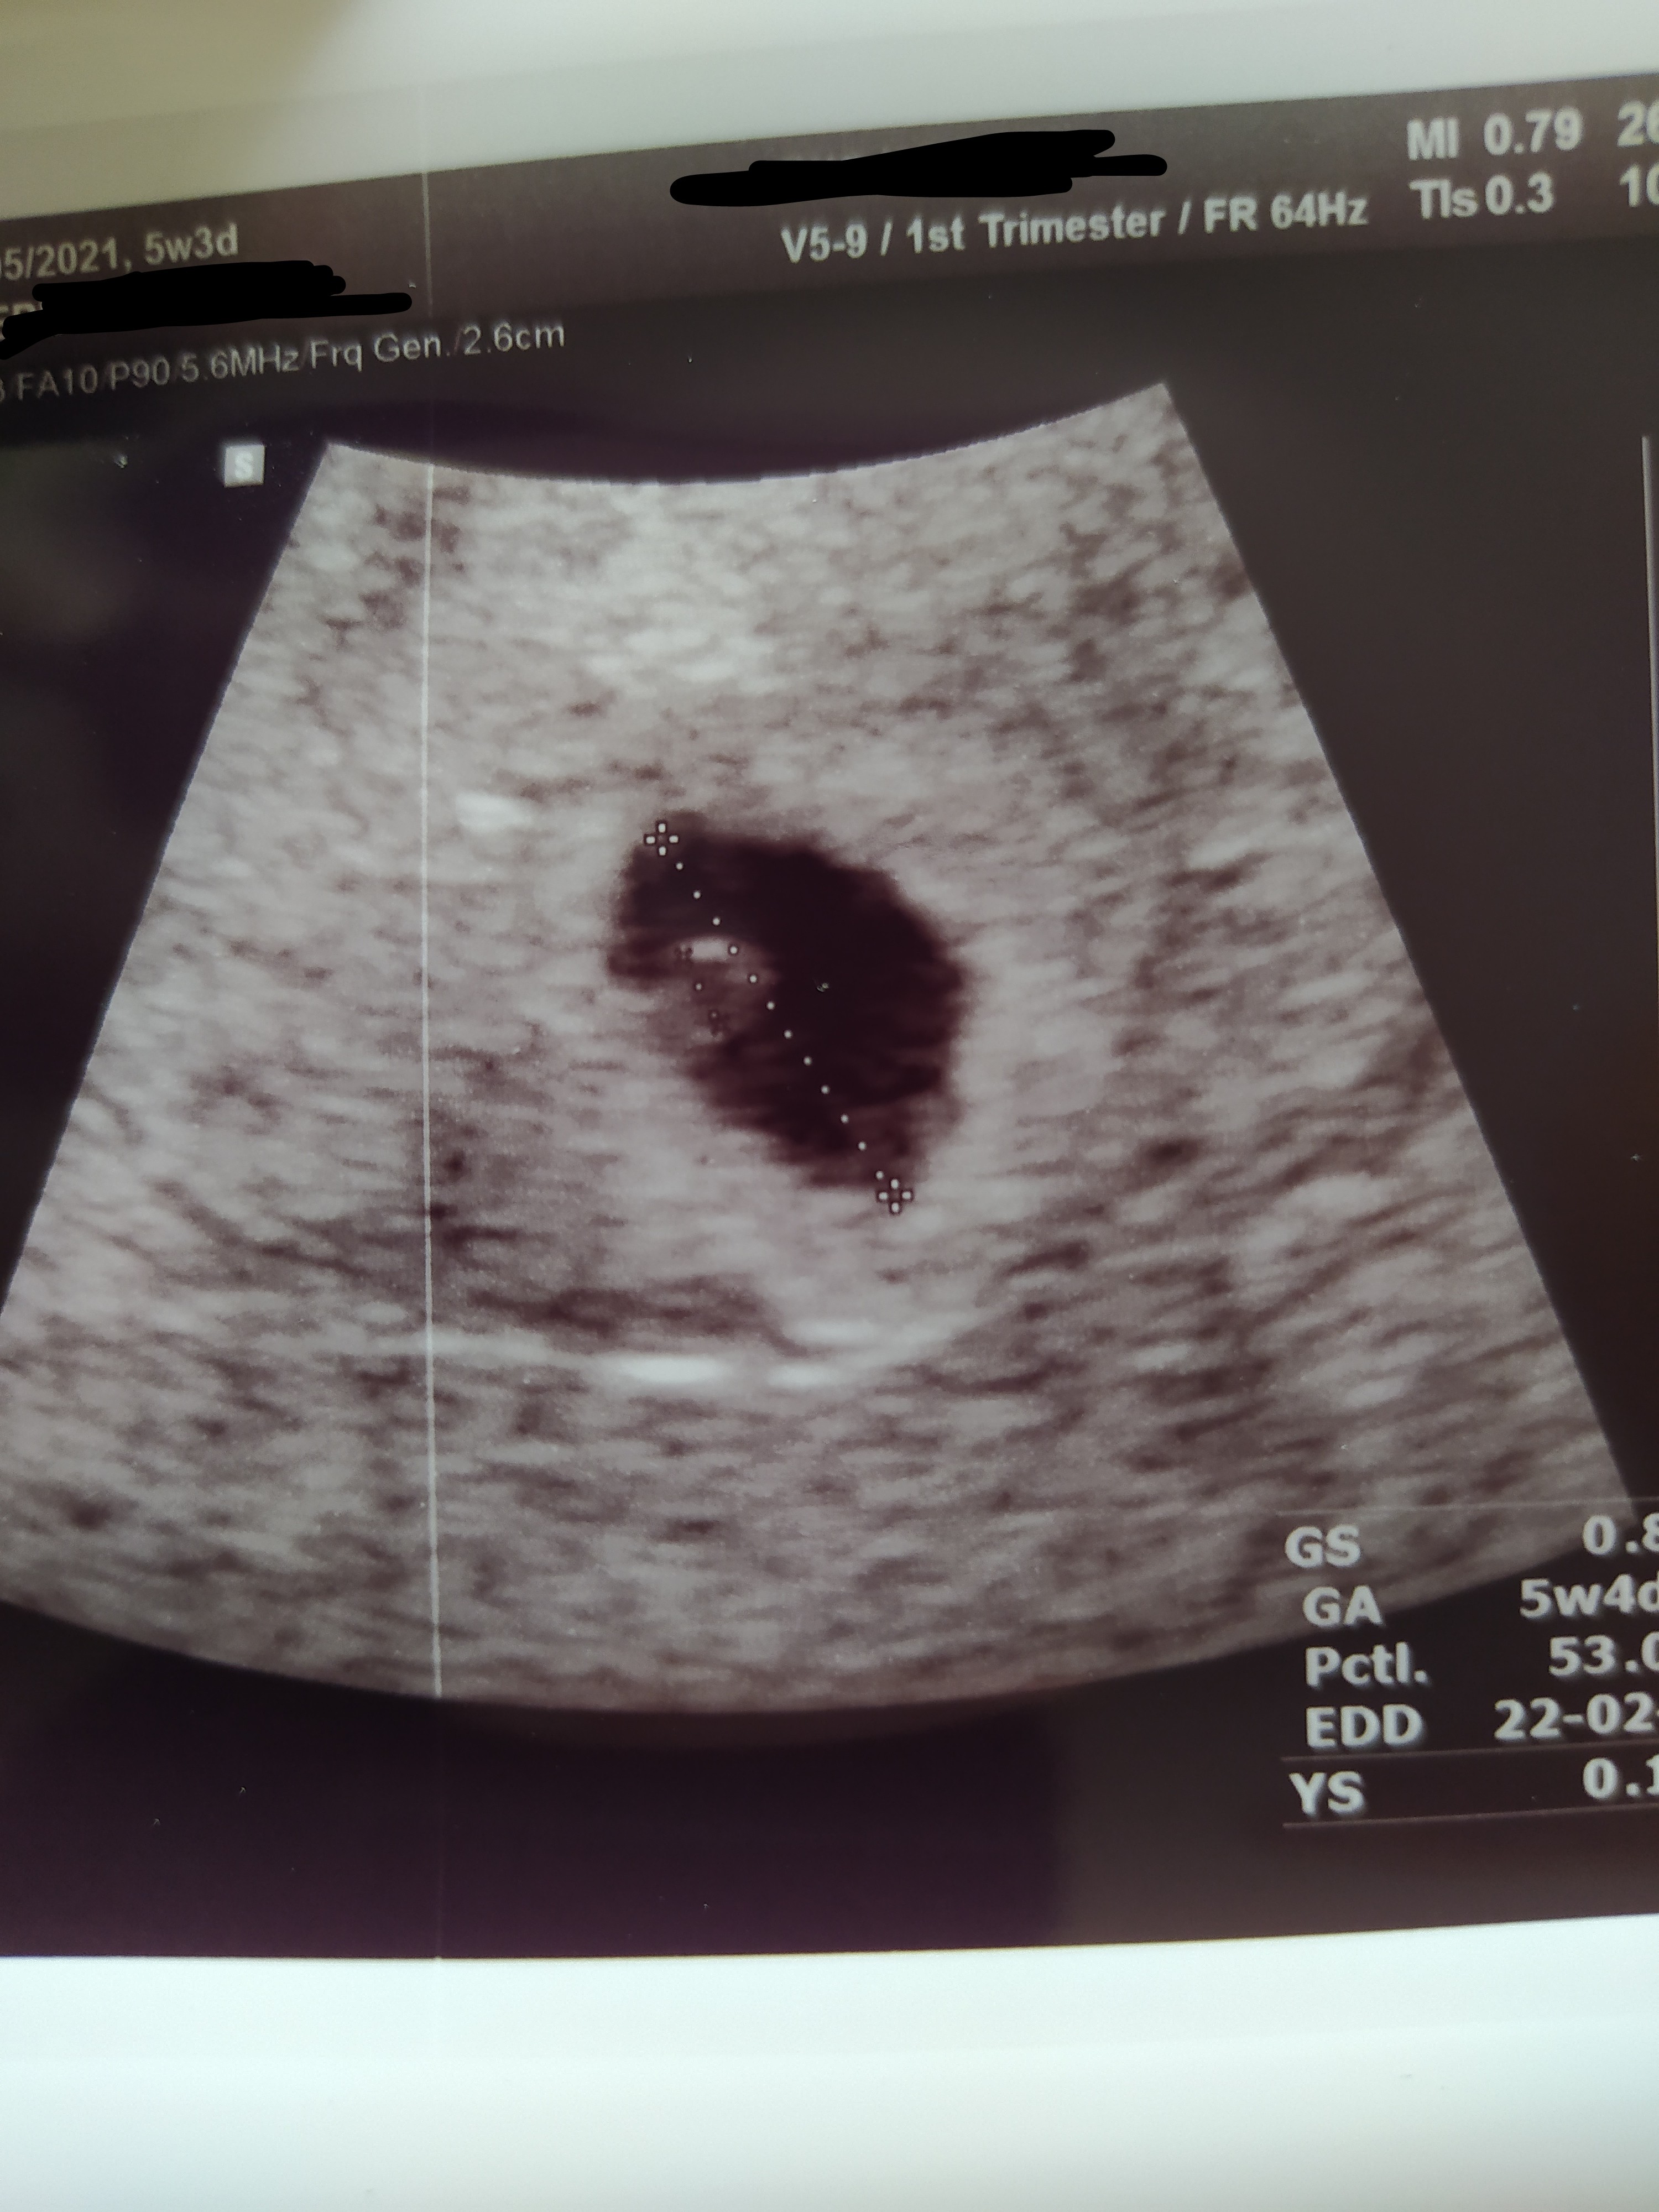

Dzisiaj byłam na wizycie 5+3, widać pęcherzyk żółtkowy i ogólnie mówi że aktualnie wszystko poprawnie. Kolejna wizyta za 2 tyg może będzie bicie serca 🤞😊Zobacz załącznik 1287549

Żadna z Was nie spotkała się że spłaszczony pęcherzyk ipęcherzykiem?

Moja poprzednia ciąża spłaszczony pęcherzyk i jeszcze zarodek w fatalnym miejscu bo w tym spłaszczeniu. Syn jak pisałam urodził się w terminie cały i zdrowy.

IMG_20210626_170932.jpg